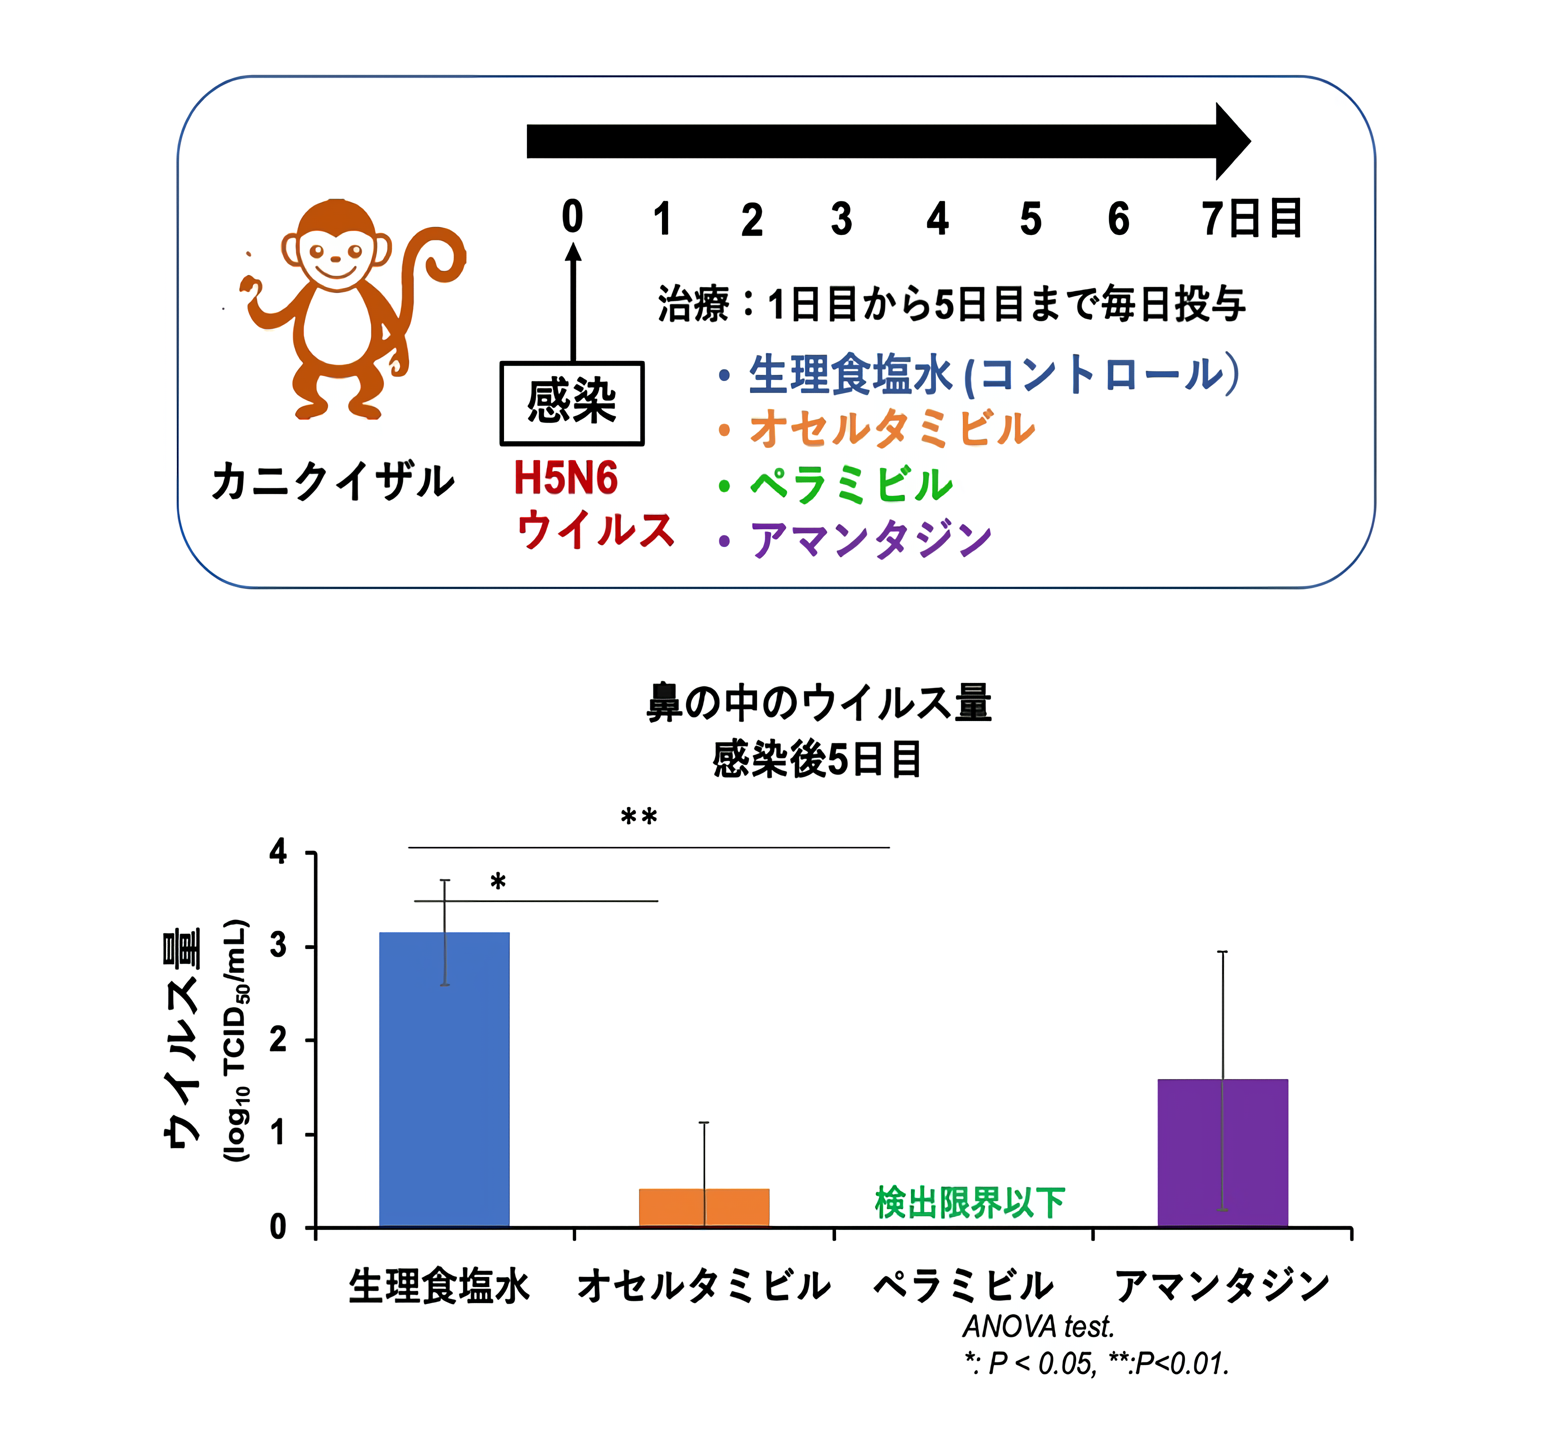

論文紹介 | 滋賀医科大学 病理学講座 疾患制御病態学部門, Fabry病│医學事始 いがくことはじめ,